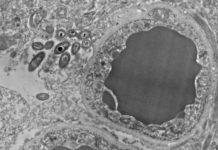

¿Por qué hay bacterias intestinales dentro del cerebro humano?

Los científicos siguen trabajando en las conclusiones de un estudio preliminar presentado hace un mes y que sugirió la existencia de un «microbioma cerebral»,...